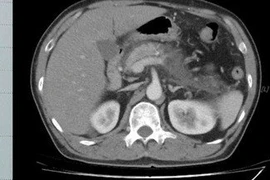

Ngày 14/1, Bệnh viện Đa khoa Trung ương Cần Thơ cho biết, Bệnh viện vừa cứu sống hai bệnh nhân bị chấn thương vùng bụng, đứt đôi dạ dày, vỡ đôi tụy, vỡ gan.